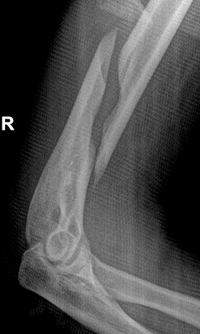

Spiral Fracture of Humerus